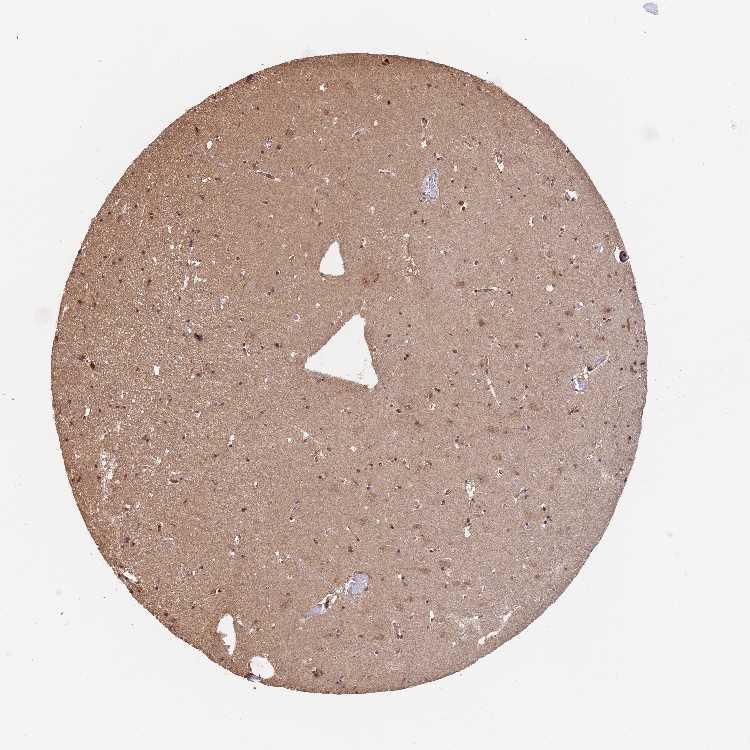

HIPPOCAMPUS - Antibody stainingi

Antibody staining in the annotated cell types in the current human tissue is reported as not detected, low, medium, or high, based on conventional immunohistochemistry profiling in selected tissues. This score is based on the combination of the staining intensity and fraction of stained cells.

Each image is clickable and will lead to virtual microscopy that enables deeper exploration of all samples and also displays staining intensity scores, fraction scores and subcellular localization as well as patient and tissue information for each sample.

Antibody HPA042123Antibody HPA048064Antibody CAB037314

Glial cells LowNot detectedNot detected

Neuronal cells MediumNot detectedNot detected